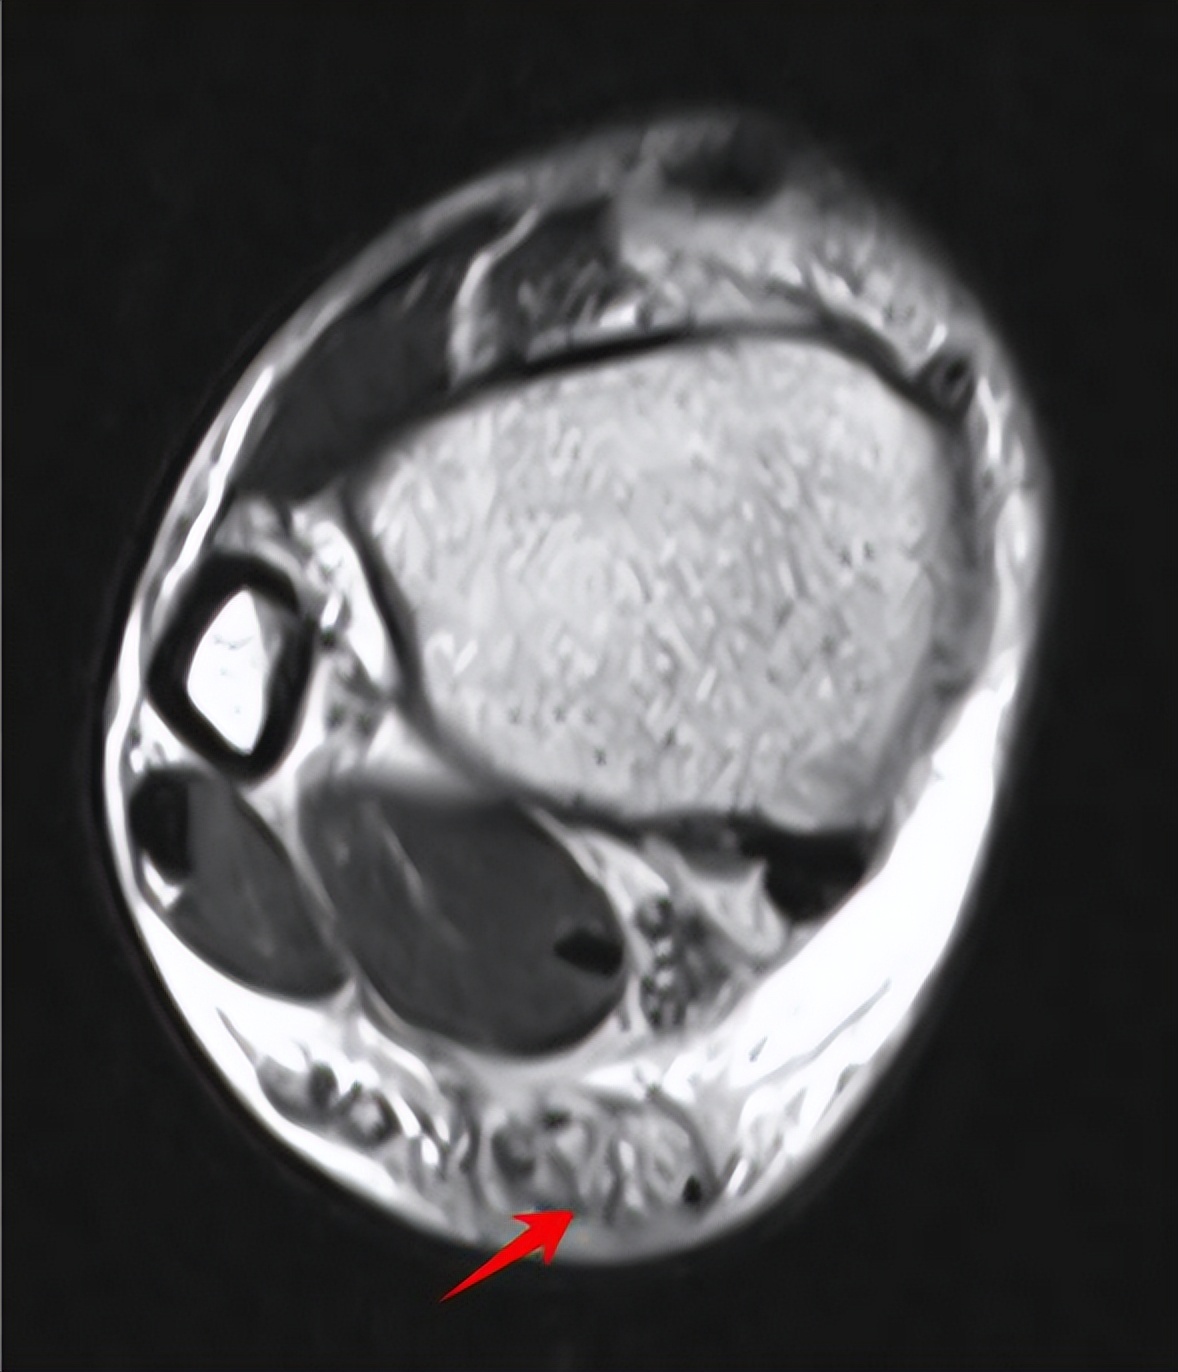

影像学检查在诊断跟腱断裂中也有举足轻重的地位,其中首选的是超声检查,肌腱超声检查是最方便、快捷且实惠的检查方式,具有较高的敏感性,通常作为初步筛查,但需要注意的是,倘若只有部分跟腱断裂,尤其是腱内断裂时,其敏感性就大大降低。而MRI检查对软组织灵敏性较高,可比较准确地显示跟腱及周围软组织情况,明确跟腱是否断裂及断裂的具体位置,且对日后手术具有指导意义。此外,普通X线片可用于判断是否有跟腱附着部位的急性撕脱骨折。